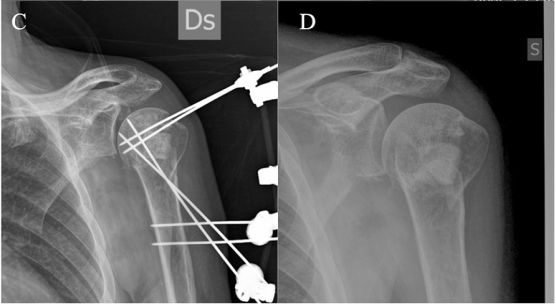

典型病例:

62岁,男性

肱骨近端外展型位移骨折,伴内侧距骨折

通过“pins-bridging-fracture”外固定架技术固定